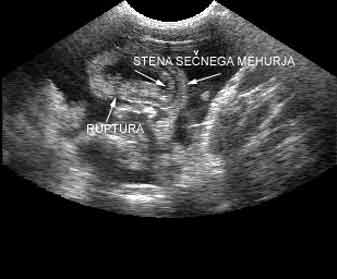

Z ultrazvočnim pregledom smo ugotovili, da je sečni mehur skoraj prazen, izven mehurja v trebušni votlini pa je nekaj proste tekočine. Glede na anamnestične podatke, smo posumili, da je morda sečni mehur počen. Z natančnim pregledovanjem mehurja smo ugotovili, da je na hrbtni strani mehurja stena prekinjena. Slika prikazuje pogled na sečni mehur. Dobro je vidna stena sečnega mehurja, ki je prekinjena; okrog mehurja pa prosta tekočina. |